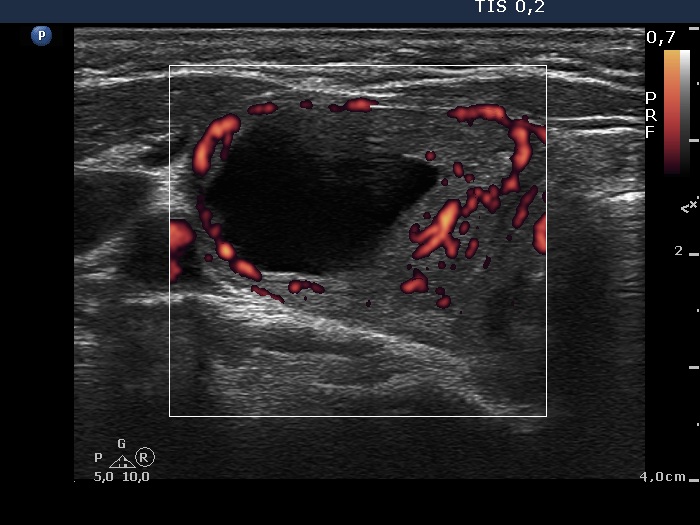

Ultrasonography. The thyroid was echonormal. There was a cystic nodule in the right lobe containing minimally hypoechogenic solid part. The lesion showed a combined intranodular and perinodular blood flow. There were smally cystic areas in the left lobe.